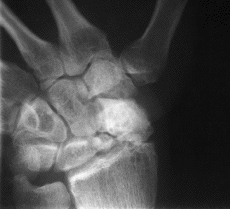

El tratamiento actual de las lesiones óseas del carpo se realiza teniendo en cuenta las estructuras ligamentosas que sostienen a este sistema,9-12reconociéndose que es la estabilidad del carpo el parámetro que va a decidir e interferir en la evolución de una lesión carpiana.8-15,20 Según estos principios, en el tratamiento de la pseudoartrosis del escafoides carpiano se considera esencial la consecución de una adecuada reducción anatómica tanto en longitud como en morfología, desviaciones angulares y desplazamiento lateral, restableciendo la estabilidad intrínseca del carpo. Según Fisk11 y Fernández8-10 puede establecerse una diferenciación entre dos tipos de pseudoartrosis: las pseudoartrosis estables, no desplazadas o sin deformidad, y las inestables, desplazadas o anguladas. Las segundas suelen presentar una deformidad radiológica típica conocida como DISI y una imagen radiológica del escafoides en proyección lateral conocida como humpback deformity (traslación volar, flexión, desviación cubital y pronación). Esta diferenciación tiene importancia tanto pronóstica como terapéutica y así sugieren que sólo es aplicable la técnica clásica de Russe en los casos de pseudoartrosis sin deformidad en flexión del escafoides, acortamiento o inestabilidad carpiana asociada, o colapso. Para el resto de situaciones el injerto triangular o trapezoidal es el idóneo para restablecer las deformidades en flexión en el plano sagital y la angulación radial deseada en el plano frontal, así como para corregir la longitud del mismo. También es importante realizar la intervención lo más precozmente posible, pues a medida que la pseudoartrosis evoluciona las alteraciones anatómicas, óseas y funcionales se incrementan y se estructuran, haciendo más difícil el restablecimiento de la congruencia articular y ligamentosa del carpo. De hecho, en la presente serie los pacientes con más alteraciones radiológicas y con artrosis carpiana incipiente, que posteriormente en las revisiones no han mejorado a pesar de la consolidación de la fractura, son aquellos en los que la inestabilidad del carpo no se ha corregido y la artrosis carpiana ha continuado desarrollándose; sin embargo, el hecho de no haber encontrado relación entre la presencia de dolor y la artrosis del carpo puede deberse al corto período de seguimiento del estudio. Así se ha observado que un buen resultado anatómico y funcional no se va a deteriorar ya con el paso del tiempo y va a permitir prevenir las secuelas tardías de artosis (Fig. 1); por otro lado, la consolidación ósea sola no es suficiente per se para la curación y desaparición del dolor.

A

BC

DFigura 1. A y B: Pseudoartrosis de 13 meses de evolución desde el traumatismo conocido con dolor de muñeca moderado. C: Tras la intervención se objetivó consolidación radiológica definitiva a las 20 semanas de evolución postoperatoria, con un ángulo escafolunar normal y un resultado funcional bueno. D: A los 3 años de evolución postoperatoria se objetiva el mantenimiento del resultado radiológico y mejoría del resultado funcional con vuelta a la actividad laboral previa.